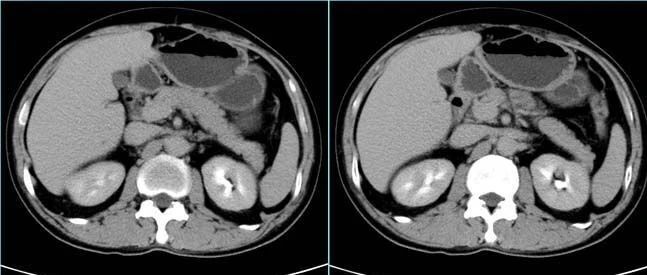

乳头状肾细胞癌!

医学影像  yxyx-app  医学影像APP,打造伴随医生快速成长的影像学习社区。与影像园(Xctmr.com)一起提供最全面的影像案例库、基础(解剖、病理、影像诊断)知识、影像技术及考题等,为医生提供最佳的医学影像参考。【所属科室】普外科【基本资料】患者,男,58岁【主诉】左后背胀痛10天【现病史】患者因“慢性支气管炎”入院,入院前10天无诱因出现左后背胀痛,局部按压及夜间疼痛明显,与吸气及活动无关,无阵发性加重及放射痛,伴咳嗽、咳少许白痰、心悸、胸闷、气短。无夜间阵发性呼吸困难...